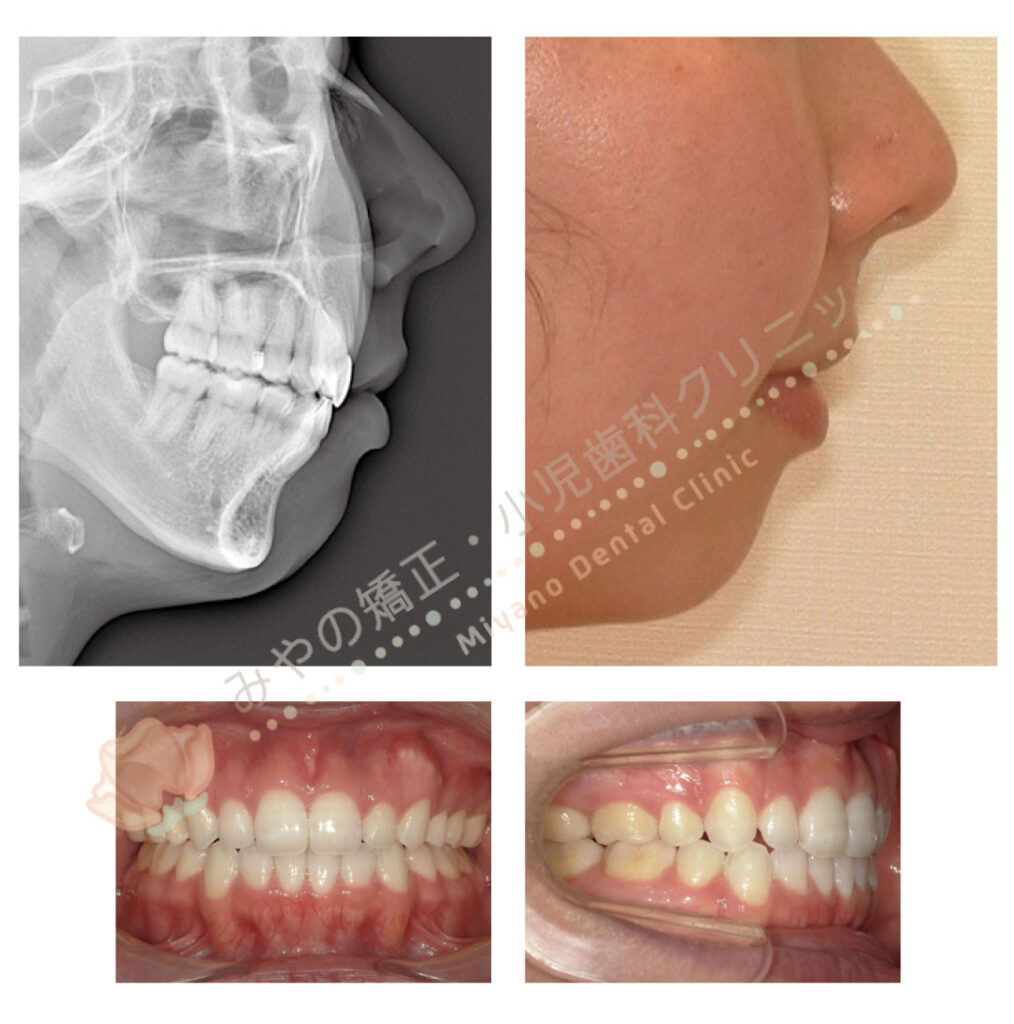

別の治療方法で改善した症例があります。

一方はマウスピース矯正で歯を抜かずに矯正治療を行った症例

もう一方はワイヤー矯正にて上下の歯を1本ずつ、計4本抜歯をして矯正治療行った症例です。

どちらの方法で治療を行っても、歯だけをみるとどちらの患者様もしっかり中に入っています。

セファロと呼ばれる横顔のレントゲン写真にてEラインを確認すると

インビザライン非抜歯では、あまり大きな変化はなく

ワイヤー矯正上下4本抜歯ではEラインがきれいに改善しているのがわかるかと思います。

矯正の目的は歯だけでなく、横顔(Eライン)の変化も重要となります。

口写真だけでは判断できないため、顔写真やセファロという横顔のレントゲン写真で確認する必要があります。

この患者様も矯正治療が終わったが、横顔はこれ以上綺麗にならないかとセカンドオピニオンにて来院されました。

この方の口腔内写真をみても、客観的に矯正治療が失敗しているとは全くもって感じることはありません。

むしろ骨格的な問題がある中、マウスピース矯正で上手に矯正治療をされているなと感じるくらいです。

それでもこの方のようにトラブルとしてセカンドオピニオンで来院されてしまいます。

矯正治療を行う上で、治療ゴールの共有や密なコミュニケーションが非常に大切となります。